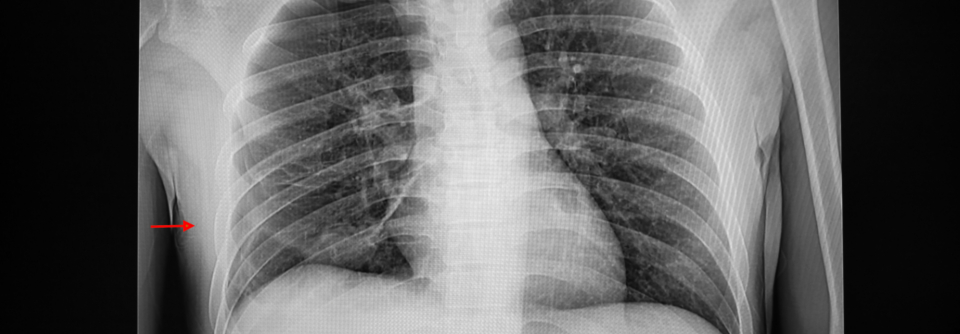

Die Entscheidung, ob es sich auf dem Röntgenbild um einen Pneumothorax handelt oder nicht, könnte schon bald eine Künstliche Intelligenz treffen. Derzeit übt sie noch – allerdings ziemlich erfolgreich.

Die Diagnose Pneumothorax wird in der Regel mittels Thoraxröntgen gestellt. Künstliche Intelligenz (KI) kann bei der Auswertung der Bilder helfen und so die Versorgung kritisch kranker Menschen verbessern und beschleunigen, schreiben der Neurologe Dr. James Hillis vom Data Science Office des Netzwerks Mass General Brigham in Boston und Kollegen. Die FDA hat bereits mehrere softwarebasierte Modelle zur Pneumothoraxerkennung zugelassen. Gemeinsam mit weiteren Forschern aus den USA und Australien testete das Team nun die Leistungsfähigkeit des einzigen kommerziell erhältlichen KI-Modells, das einen Pneumothorax und einen Spannungspneumothorax unterscheiden kann. Der Algorithmus war zuvor an mehr als 750.000 Thoraxröntgenaufnahmen trainiert worden.

Das Analysekollektiv bildeten 985 Röntgenaufnahmen von Erwachsenen (Durchschnittsalter 60,8 Jahre) aus den Archiven von vier US-Kliniken. Zunächst werteten drei erfahrene Thoraxradiologen die Bilder aus: In 435 Fällen (44,2 %) diagnostizierten sie Pneumothoraces, darunter 128 Spannungspneumothoraces, bei den übrigen 550 Aufnahmen (55,8 %) schlossen sie diese Lungenkomplikation aus.

Das KI-Modell identifizierte sowohl jegliche Pneumothorax-Fälle als auch die Spannungspneumothoraces mit hoher Treffsicherheit: Die sogenannte Area Under the Curve betrug jeweils mehr als 0,95, bei einer Sensitivität und Spezifität von über 90 %. Die Diagnosegenauigkeit war dabei unabhängig von demografischen (Alter, Geschlecht) und technischen Parametern (Hersteller, Patientenposition, Röntgenprojektion) sowie von der Pneumothoraxausdehnung. Zusatzbefunde wie ein Pneumomediastinum, ein subkutanes Emphysem oder eine Interkos­taldrainage reduzierten allerdings die Spezifität.

Die Forschenden halten das KI-Modell für ein wertvolles Triage­instrument, das beispielsweise dabei helfen kann, vital gefährdete Personen priorisiert zu behandeln. Studien müssen nun klären, inwiefern sich der Algorithmus auf den klinischen Arbeitsfluss und die Behandlungsergebnisse auswirkt.